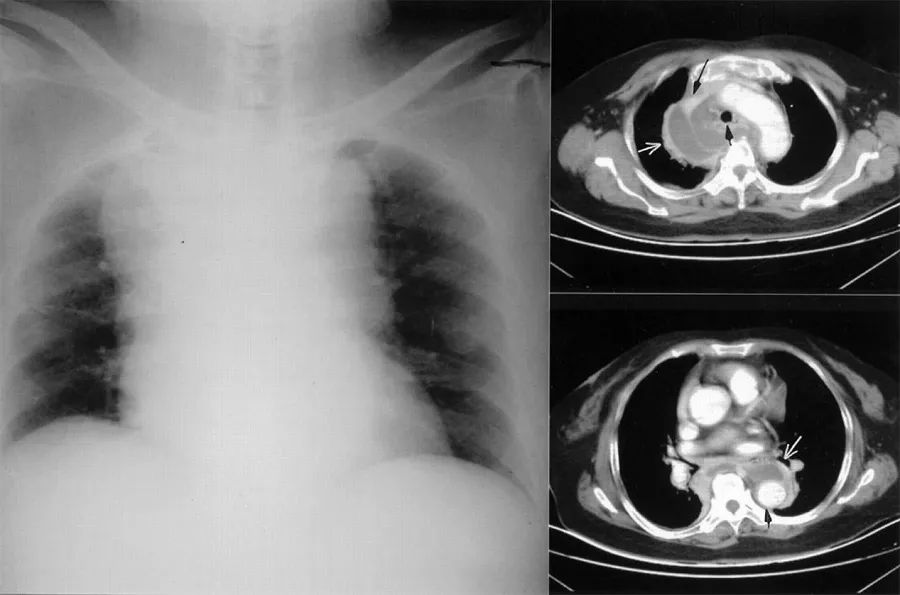

患者男性,50岁,自行车运动员,有心血管疾病家族史,没有其他危险因素。患者自述在骑行上坡时出现左侧胸部胸痛,被迫停下来。家庭医生认为患者为流感样综合征,但患者的妻子决定征询心脏病专家的意见。患者在心脏专科接受了详细的临床检查,没有发现特别的异常情况,心电图(图7)和超声心动图检查都是正常的。因此,心脏病专家得出非典型胸痛的结论,建议“不需要进一步的检查”。

图7 患者静息心电图

幸运的是,患者在一周后在另一家诊疗中心接受运动心电图检查,检查时发现了V4-V6导联ST段压低(图8),并伴有胸痛,表现为典型的心绞痛。恢复时,心电图仍提示V4-V6导联ST段明显压低(图9)。进一步安排了冠状动脉造影检查(图10),结果显示左前降支90%闭塞(TIMI 1级),后行血管成形术放置药物洗脱支架(DES)。患者在3个月后恢复正常的体力活动(骑车)。

图8 运动试验检查时异常心电图

图9 运动试验后恢复时异常心电图

图10 冠脉造影显示狭窄的前降支